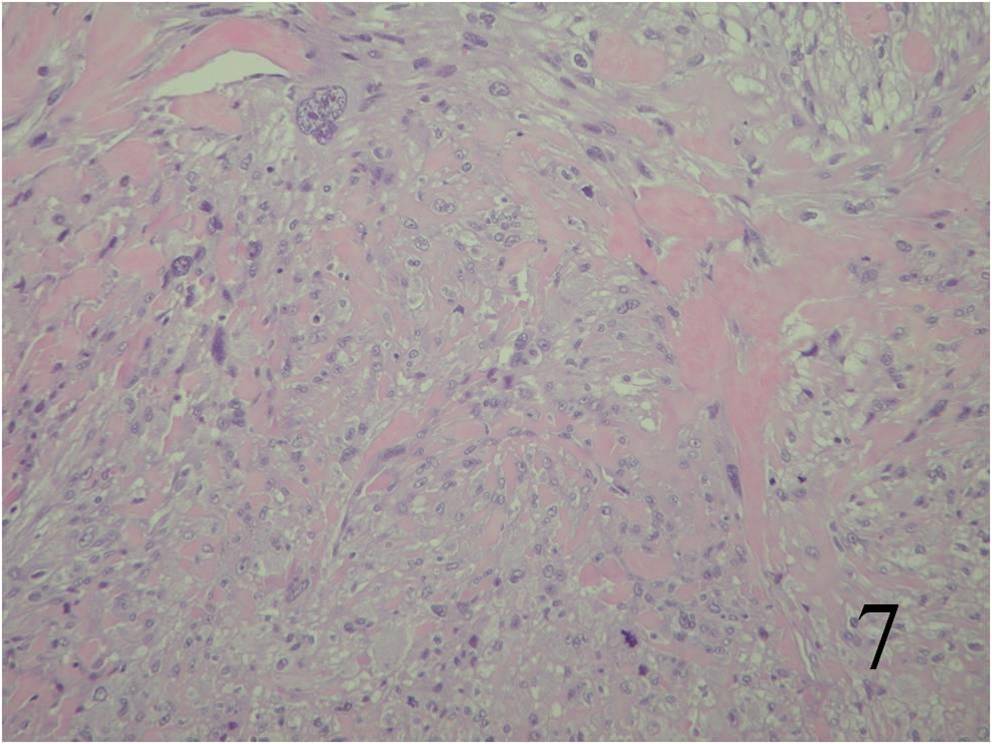

Large variation in differentiation, from obvious smooth muscle differentiation to an appearance similar to MFH (Fig. 7,8)

Fig. 7 Microscopic: Low and High (Fig. 8) power magnification of a leiomyosarcoma showing palisading spindle cells; with eosinophilic cytoplasm. Immunohistochemical stains for leiomyosarcoma are positive stain for actin (Fig. 9) and desmin (Fig. 10)